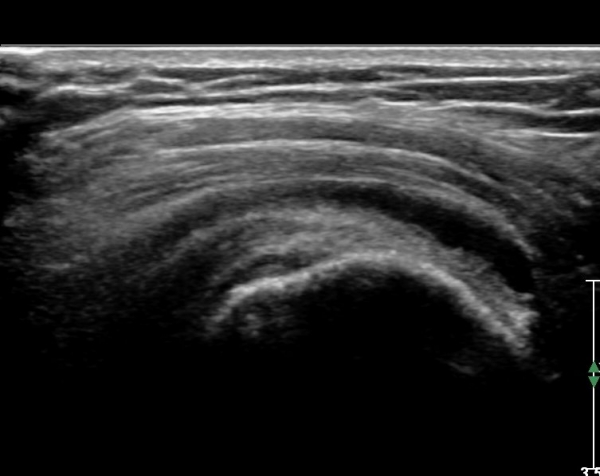

±ØÇ졂 Á¾´Ü¸é °Ë»ç¿¡¼­ Àá¾×³¶³» ¼ö¾×Àú·ù°¡ °üÂûµÇ°í(»çÁø 9) ÅÒÃËÀÚ¸¦ Á¶±Ý ³»ÃøÀ¸·Î

À̵¿ÇÏ´Ï  ±Ø»ó°ÇÀÌ ¼Ò½ÇµÇ°í ¼ö¾×Àú·ù°¡ °üÂûµÈ´Ù(»çÁø 10).

È¸Àü±Ù°³ Ⱦ´Ü¸é°Ë»ç¿¡¼­ ±Ø»ó°Ç ³»ÃøºÎ ºÎºÐ °á¼ÕÀÌ °üÂûµÇ°í(»çÁø 11) ŽÃËÀÚ¸¦ Á¶±Ý

¸»´ÜÀ¸·Î À̵¿ÇÏ´Ï ±Ø»ó°Ç ³»ÃøºÎ ÀüÃþÆÄ¿­ÀÌ °üÂûµÈ´Ù(»çÁö 12).